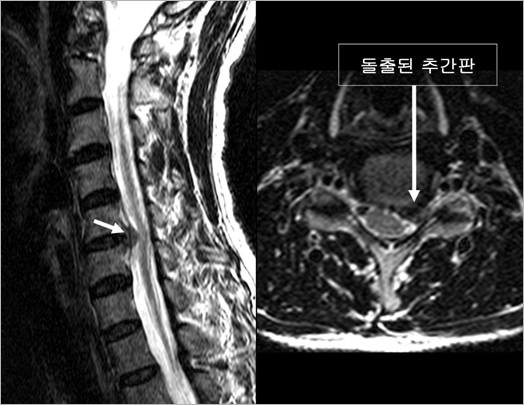

| 이렇듯 중요한 역할을 하는 추간판이 말썽을 일으키는 경우가 있는데 가장 흔한 예가 소위 "목디스크(정확한 표현은 아닙니다)"라 불리는 병입니다. "목디스크"란 추간판이 노화되어, 신경이 지나는 척추체 뒤쪽 공간으로 돌출됨으로써 팔다리로 가는 굵은 신경 줄기인 척수(脊髓)를 누르거나, 어깨 혹은 팔로 가는 작은 신경 줄기인 신경근(神經根)을 누르는 병입니다(그림 4). 비수술적인 치료에도 증상이 호전되지 않으면 할 수 없이 수술이 필요한데, 주로 사용하는 방법이 돌출된 부위를 포함하여 추간판 전체를 제거하는 것입니다. |

| • 그림 4 돌출된 추간판이 척수와 신경근을 누르고 있는 모습 |